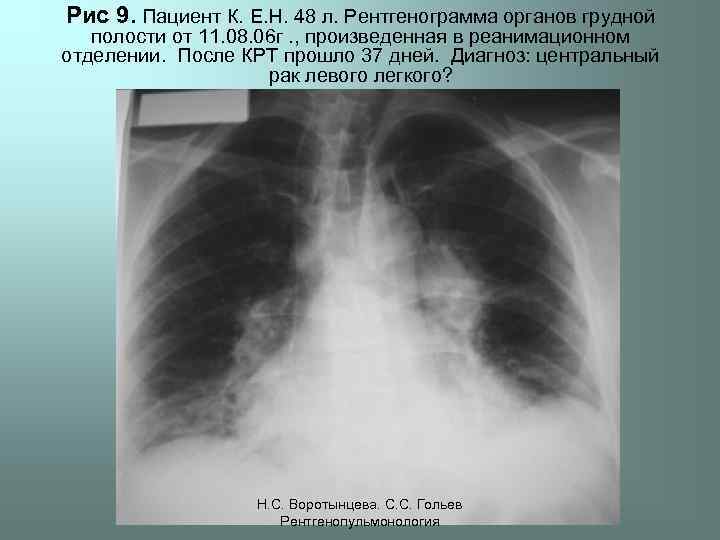

Рис 9. Пациент К. Е. Н. 48 л. Рентгенограмма органов грудной полости от 11. 08. 06 г. , произведенная в реанимационном отделении. После КРТ прошло 37 дней. Диагноз: центральный рак левого легкого? Н. С. Воротынцева. С. С. Гольев Рентгенопульмонология